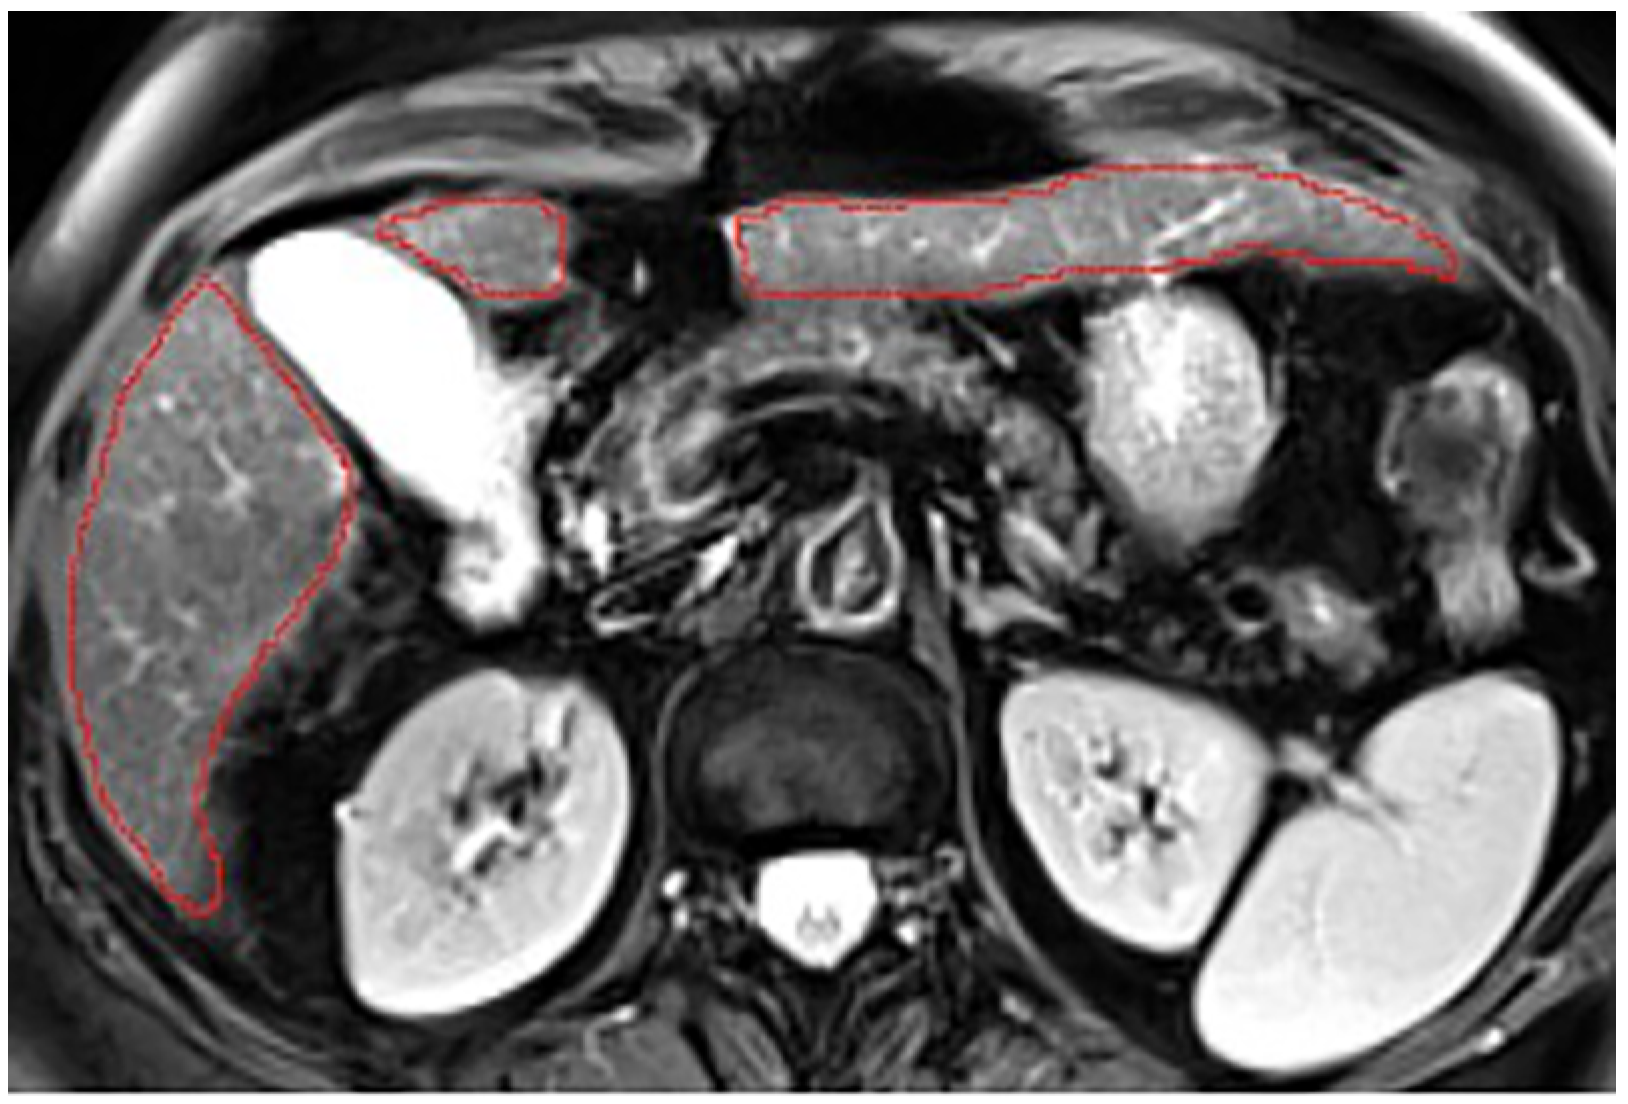

Appendix A.5. Multi-Part Liver Parenchyma